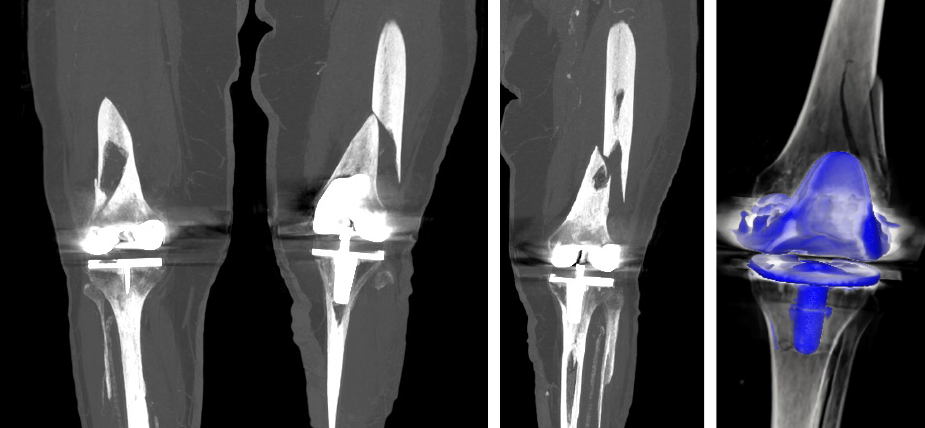

FRACTURAS PERIPROTÉSICAS

Ocurren justo alrededor de una prótesis de cadera y/o rodilla ya colocada. Algunas fracturas se pueden arreglar mediante osteosíntesis, que consiste en fijar el hueso con tornillos, placas o clavos, para que vuelvan a unirse y recuperen su función.

En otros casos, puede ser necesario reemplazar parcial o totalmente la prótesis.

La intervención busca estabilizar la zona y facilitar la recuperación, permitiendo que el paciente vuelva a caminar lo antes posible.